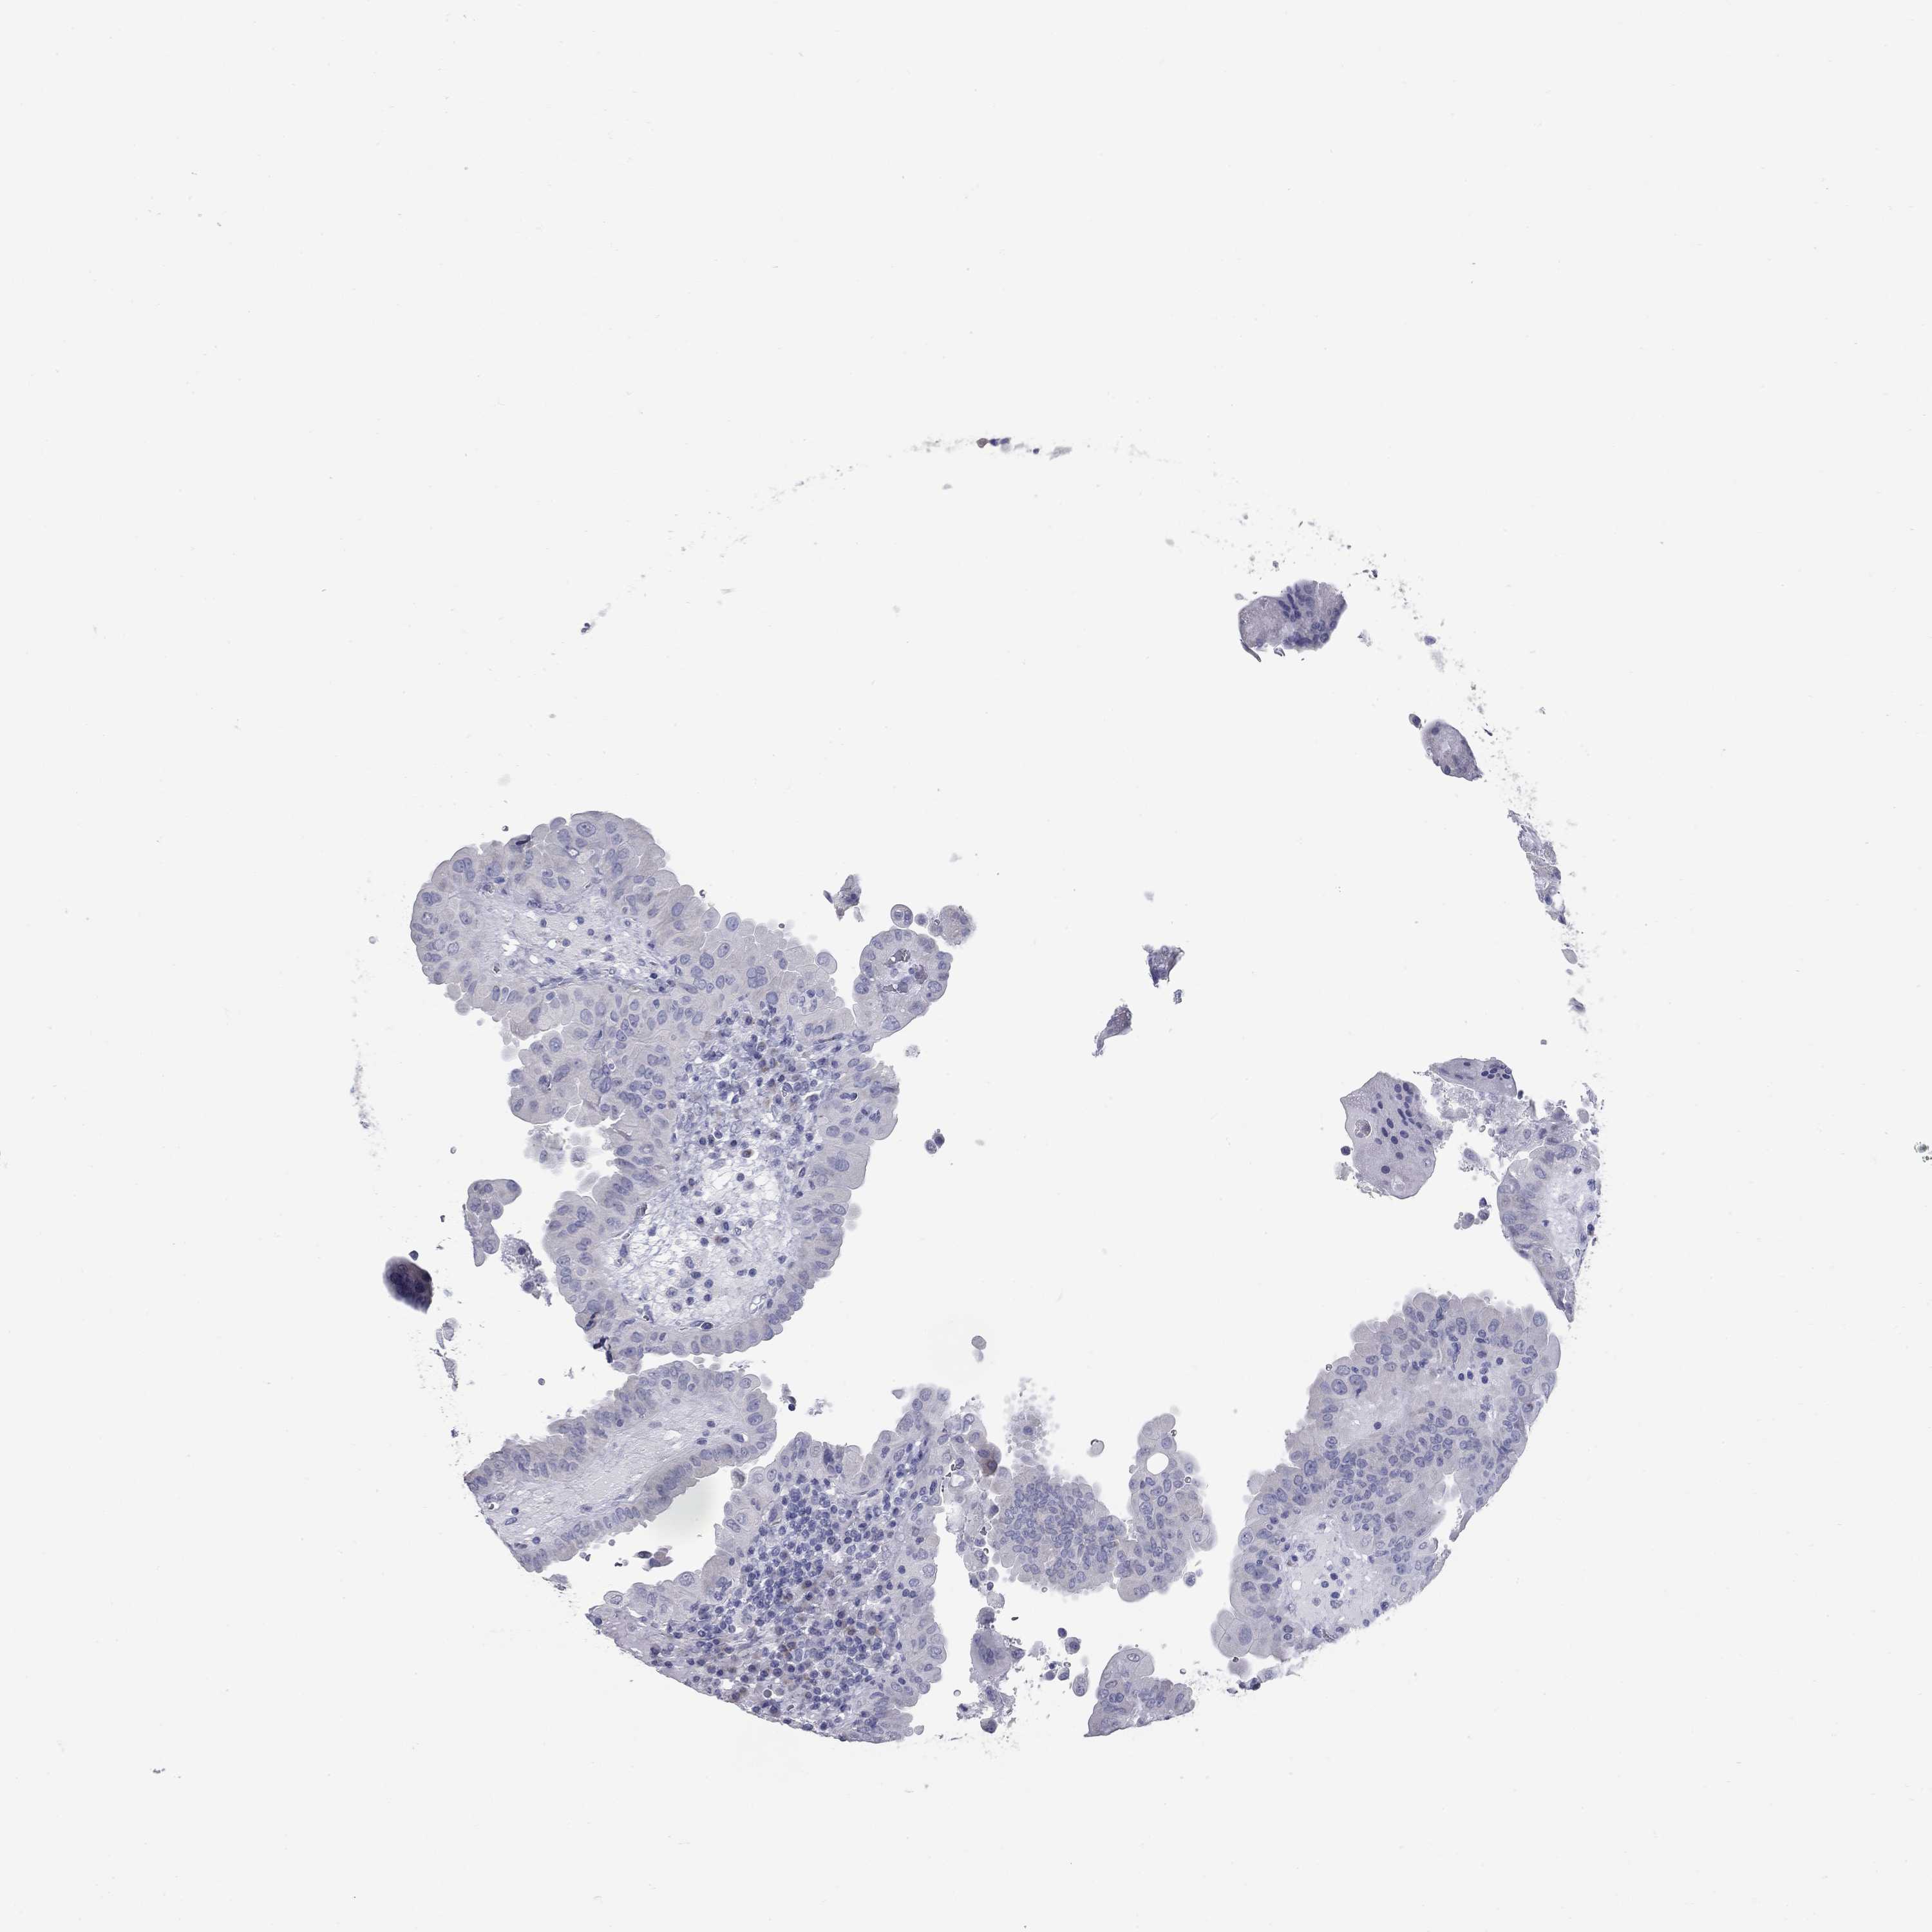

THYROID CANCER - Protein expressioni

A mouse-over function shows sample information and annotation data. Click on an image to view it in a full screen mode. Samples can be filtered based on level of antibody staining by selecting one or several of the following categories: high, medium, low and not detected. The assay and annotation is described here.

Note that samples used for immunohistochemistry by the Human Protein Atlas do not correspond to samples in the TCGA dataset.

Antibody stainingi

Antibody staining in the annotated cell types in the current human tissue is reported as not detected, low, medium, or high, based on conventional immunohistochemistry profiling in selected tissues. This score is based on the combination of the staining intensity and fraction of stained cells.

Each image is clickable and will lead to virtual microscopy that enables deeper exploration of all samples and also displays staining intensity scores, fraction scores and subcellular localization as well as patient and tissue information for each sample.

Antibody HPA014429

Staining

High

Medium

Low

Not detected

Intensity

Strong

Moderate

Weak

Negative

Quantity

>75%

75%-25%

<25%

None

Location

Nuclear

Cytoplasmic/membranous

Cytoplasmic/membranous,nuclear

Papillary adenocarcinoma, NOS

Follicular adenoma carcinoma, NOS